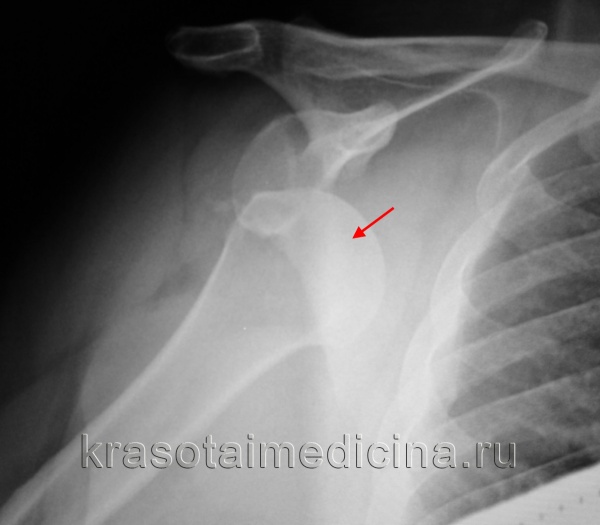

Для более точной оценки состояния плотных структур назначают рентгенографию плечевого сустава. При этом может определяться дефект по заднебоковой поверхности головки плечевой кости (обнаруживается только при специальных укладках с ротацией плеча, иногда для выявления патологических изменений необходимо сделать несколько снимков). Возможно увеличение расстояния между верхней частью головки плеча и акромионом, а также повреждение края суставной впадины.

- Рентгенографию плечевого сустава. При этом можно выявить дислокацию головки плечевой кости и некоторые другие патологические изменения. . Определение степени повреждения суставной губы (повреждение Банкарта), наличия сопутствующий мягкотканных повреждений. с 3D реконструкцией. Для уточнения величины костного дефекта, выбора возможных вариантов лечения.